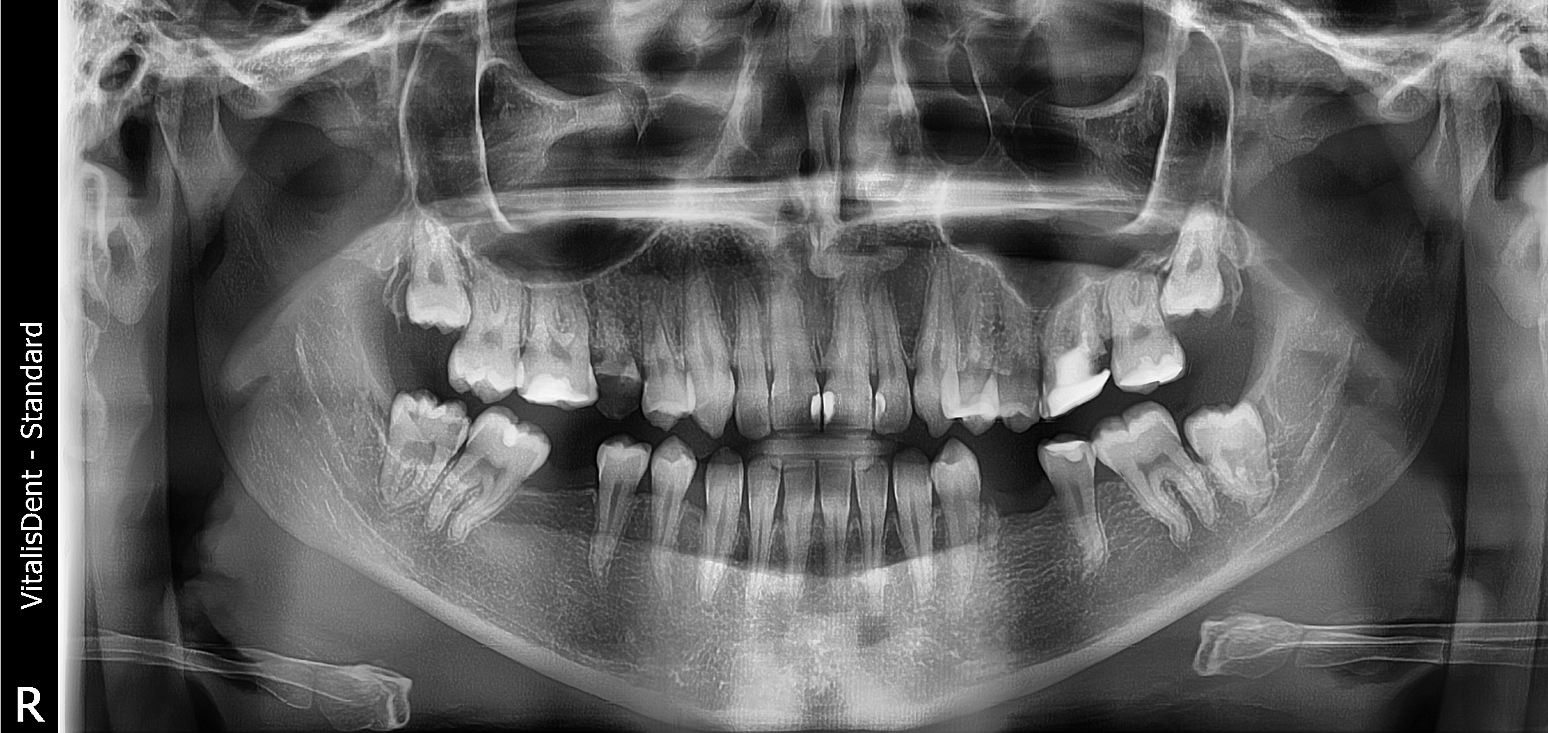

PANORAMIC

Investigație radiologica dentară care utilizează razele X pentru crearea unei imagini de ansamblu a întregii cavități orale.